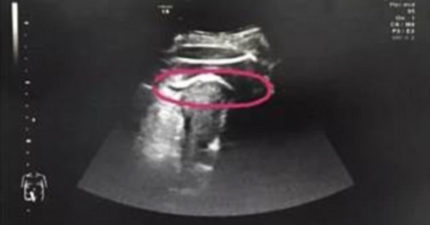

孕婦突然腹部劇痛昏迷快死掉,超音波一照「一條無影腳把子宮踢出一個洞」!